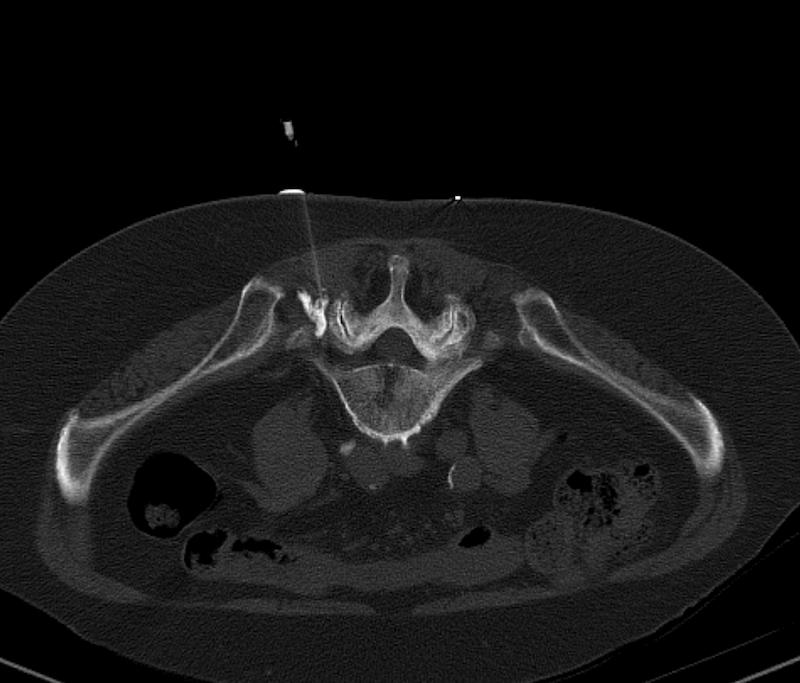

• PRT

Die periradikuläre Therapie (PRT) ist eine mögliche Therapieform bei (chronischen) Rückenschmerzen.